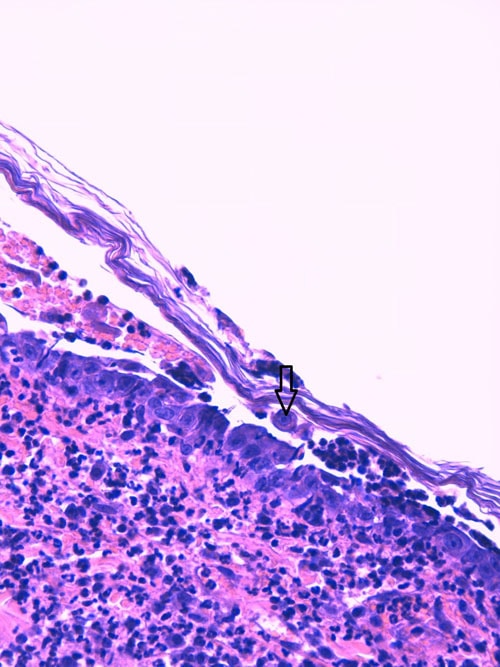

- les biopsies cutanées (LAPVSO) montrent également des vésiculo-pustules contenant des cellules acantholytiques, ainsi que des éléments PAS-positifs au sein des croûtes, évoquant fortement des hyphes mycéliennes (Photos 6 à 8).

Biopsie d’une lésion pustuleuse du pavillon auriculaire (X40, LAPVSO) Visualisation de cellules acantholytiques (X400, LAPVSO) Visualisation d’hyphes mycéliennes dans les couches superficielles (X1000 PAS, LAPVSO)

Photos 6 à 8 : Examen histopathologique montrant l’acantholyse dans les pustules et les hyphes mycéliennes au sein des croûtes - la recherche virale sur biopsie cutanée (PCR, Scanelis) est négative pour l’herpesvirose